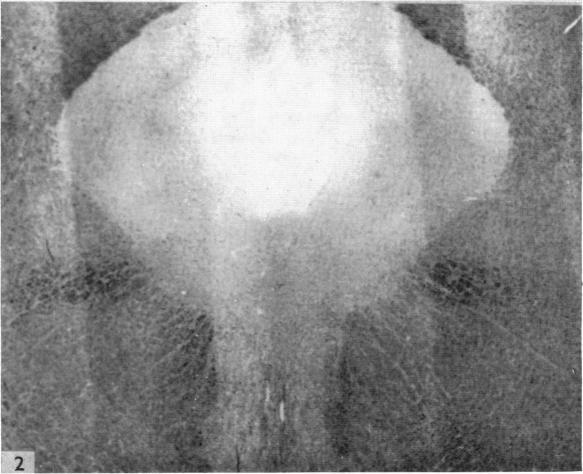

The dorsal trigeminal tract in the rhesus monkey.

J Anat. 1957 Jan;91(1):82-90.